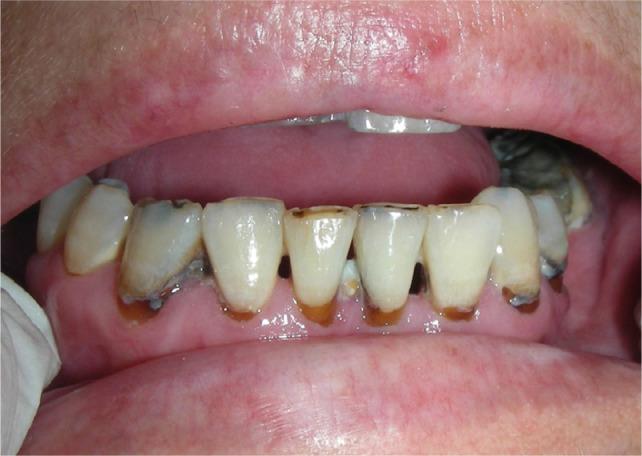

Graft-versus-host disease (GVHD) is a complication of haematopoietic stem cell transplantation (HSCT). GVHD may also develop following solid transplants or blood transfusions if white blood cells are transferred. GVHD affects multiple organs, including the oral tissues.

Acute GVHD may manifest in the oral mucosa; however, it often develops immediately following HSCT when routine dental treatment is postponed. Chronic GVHD may manifest in the oral mucosa, the salivary glands and the musculoskeletal compartment. It may indirectly affect the teeth and the oral flora, putting the patient at risk for infections. Importantly, GVHD poses an increased risk for oral cancer.

移植物抗宿主病(GVHD)是造血干细胞移植(HSCT)的一种并发症。如果白细胞被转移,GVHD 也可能在实体器官移植或输血后发生。GVHD 影响多个器官,包括口腔组织。

急性 GVHD 可能在口腔黏膜中表现出来;然而,它通常在 HSCT 后立即发生,此时常规的牙科治疗被推迟。慢性 GVHD 可能在口腔黏膜、唾液腺和肌肉骨骼部位表现出来。它可能会间接影响牙齿和口腔菌群,使患者面临感染的风险。重要的是,GVHD 增加了口腔癌的风险。